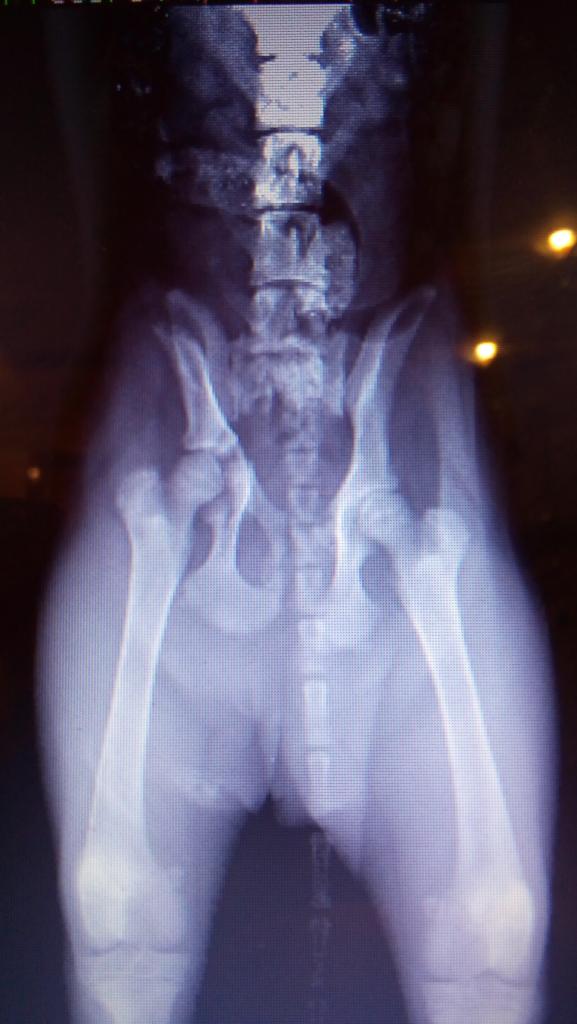

Позавчера днем собака, девочка 6 месяцев была сбита машиной ОДЕССА, ул. Невского. Перелом таза, перелом подвздошной кости. Вертлюжной впадины, седалищной кости, смещение по кресцовому сочленению, травма мочевого пузыря. Первая помощь оказана, но необходима срочная операция. огромная просьба всех неравнодушных оказать материальную помощь. На операцию предположительно надо 6000 гр. можно в клинику vita ОДЕССА , можно на карту привата - 5168757371721533. Куратор Светлана. 0969806055